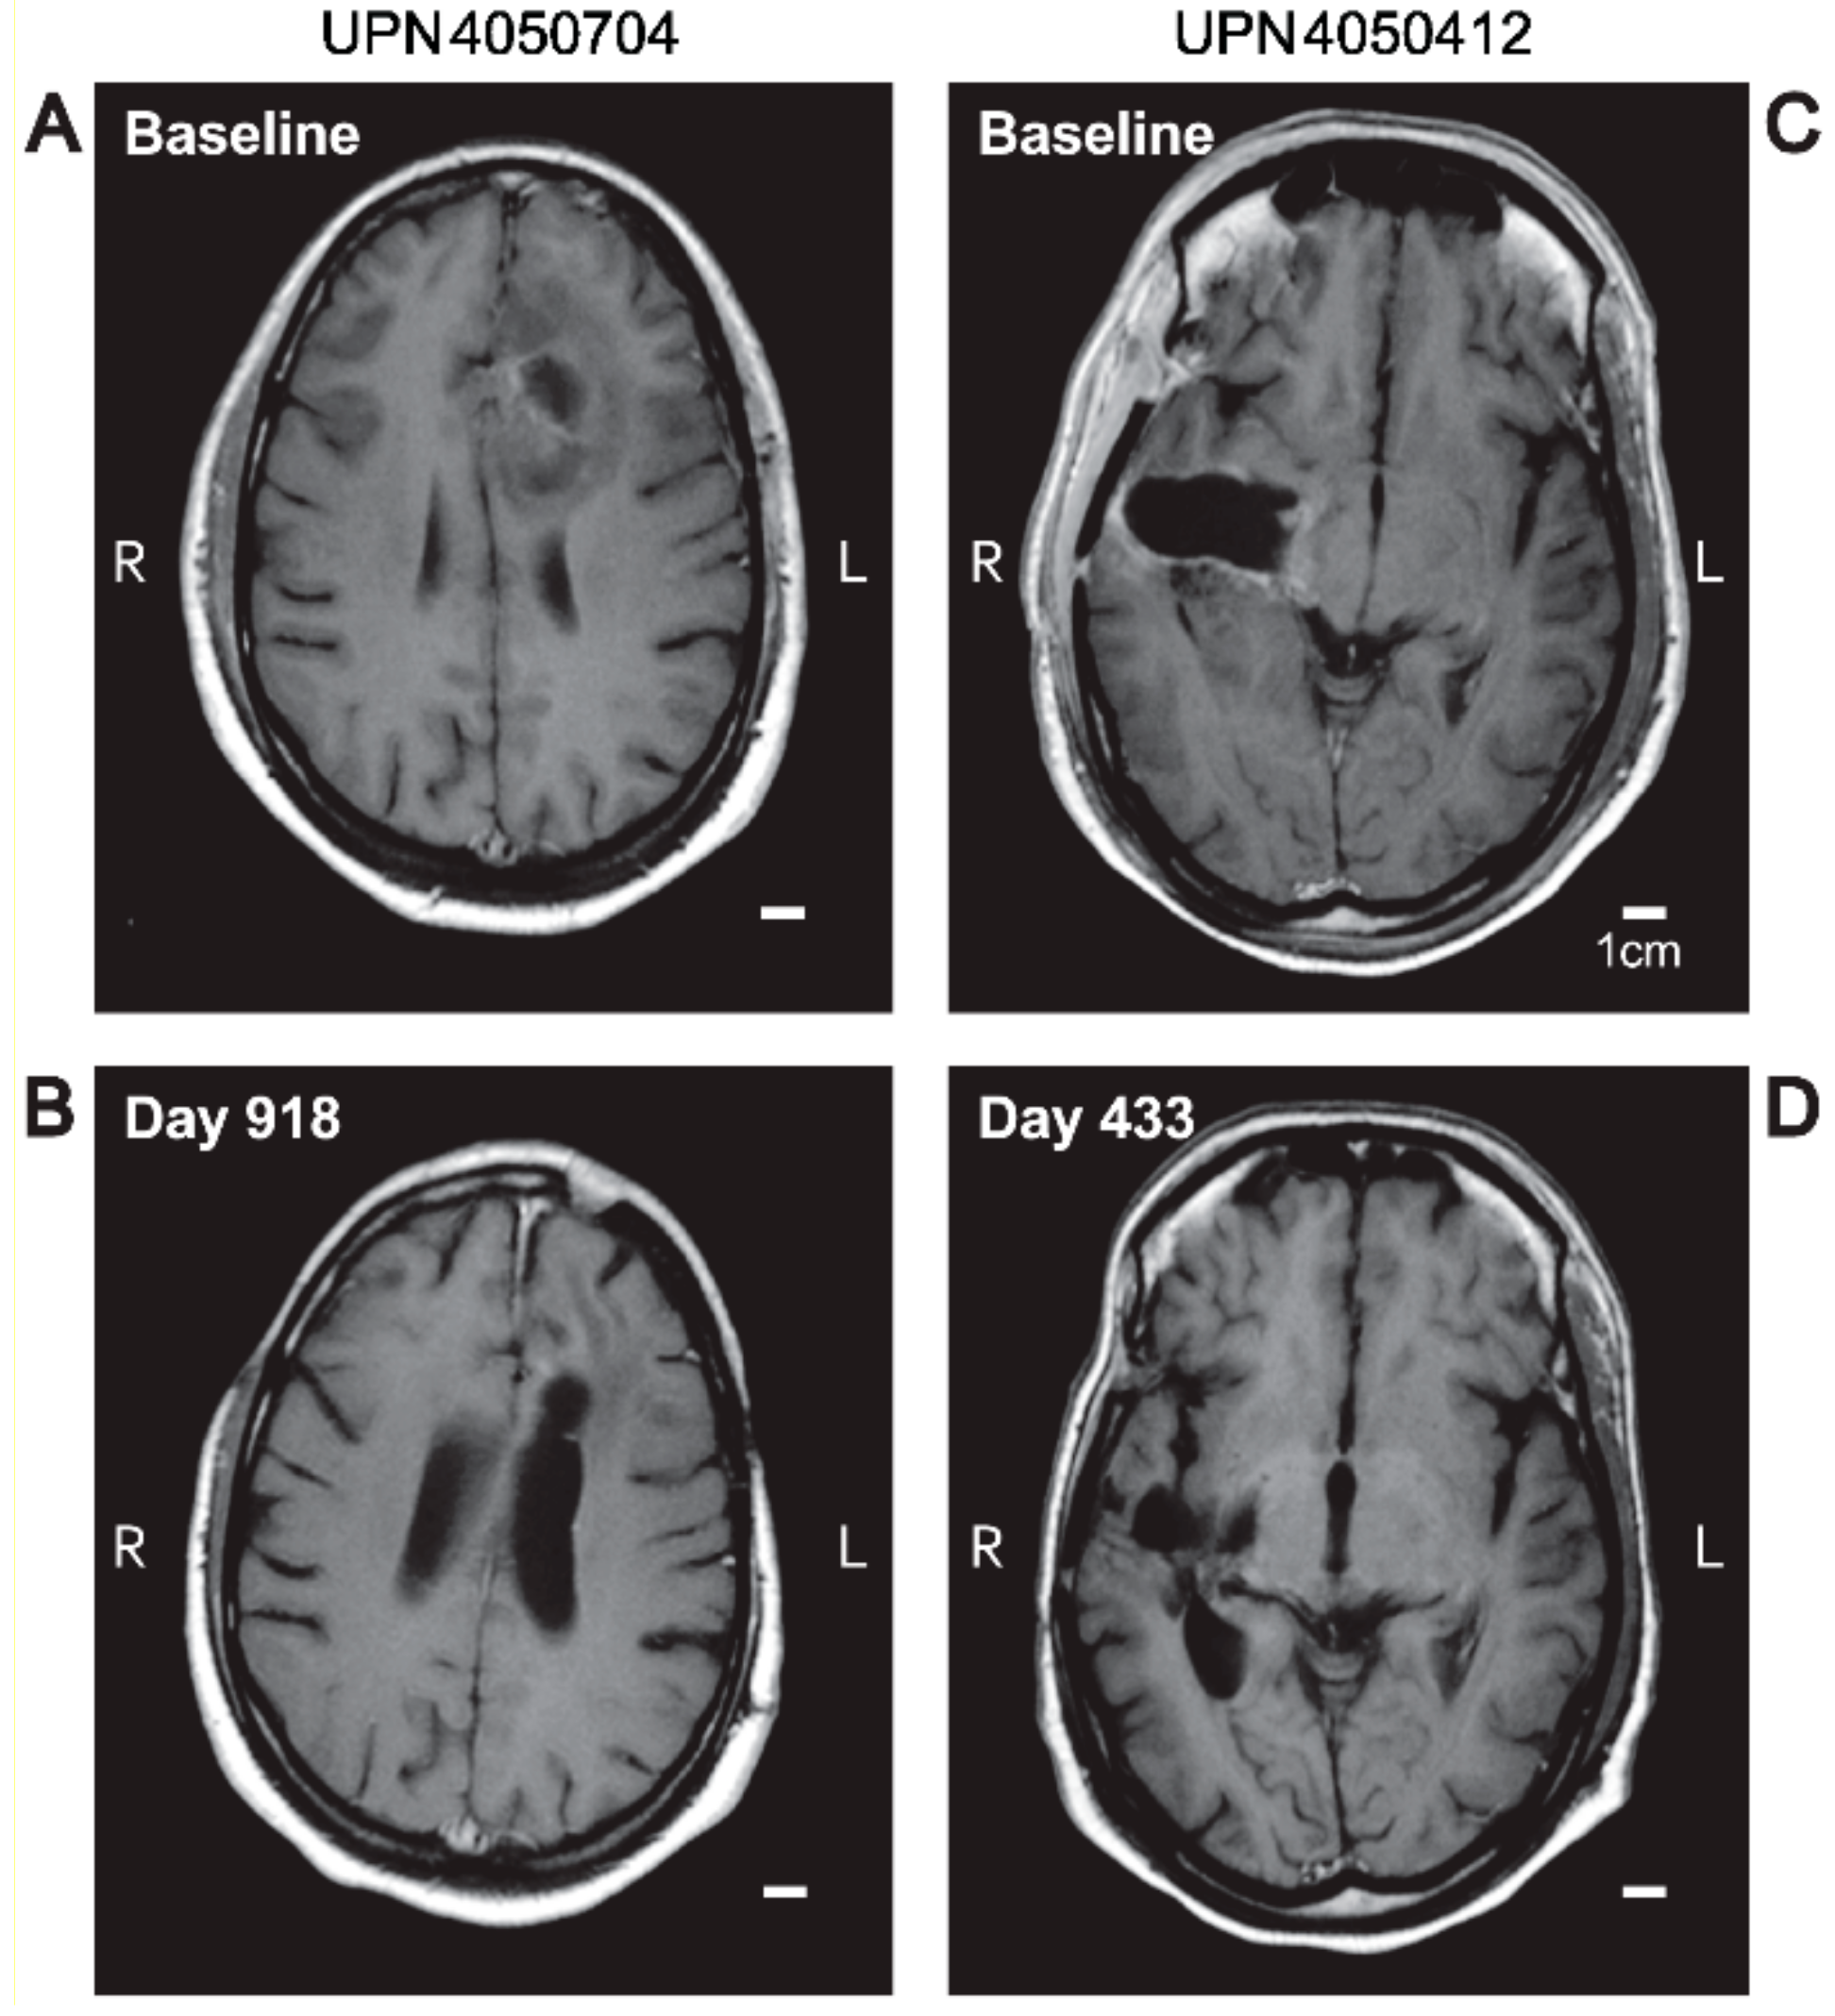

3.3. Edema and Pseudo-Progression in OT101-Yreated Target HGG Lesions